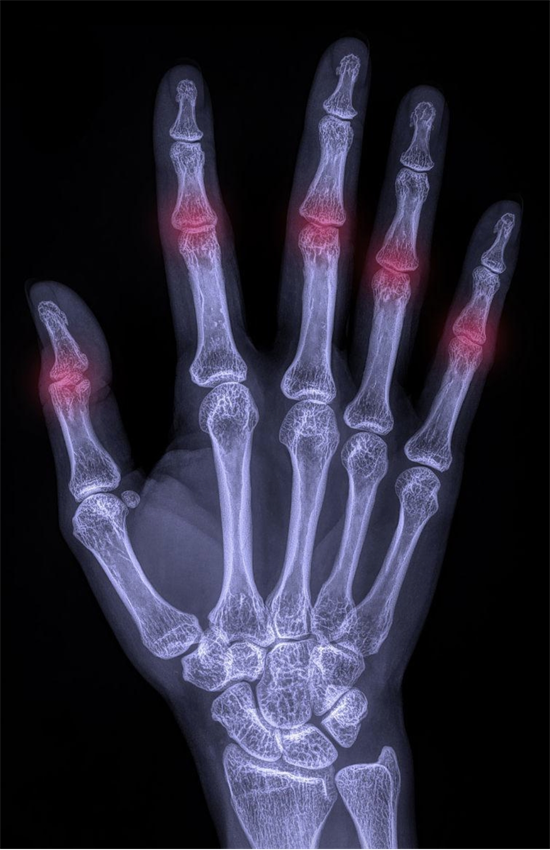

疑似手部掌、指关节骨关节炎(OA)患者应首选X线检查,手部OA标准X线检查为双手正位X线片,主要在受累指间关节、掌指关节或第一腕掌关节处可见OA典型X线表现。

受累关节在X线片上的三大典型表现:非对称性关节间隙变窄、关节边缘骨赘形成以及软骨下骨硬化和(或)囊性变。尽管X线检查不能直接显示软骨或软组织的情况,但关节间隙可以用于推测软骨损伤严重程度。除上述典型表现外,部分患者X线片可显示不同程度的关节肿胀、关节内游离体甚至关节变形。